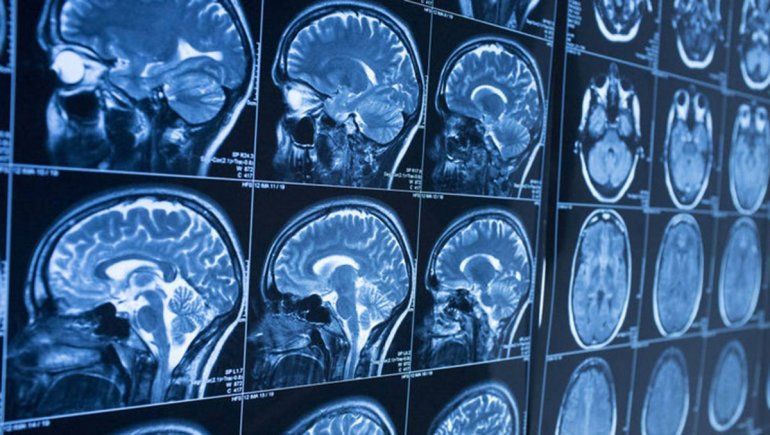

Las personas que desarrollan la enfermedad de Parkinson antes de los 50 años pueden haber nacido con células cerebrales desordenadas que no se detectaron durante décadas, según una nueva investigación del Centro Médico Cedars-Sinai. La investigación, publicada en la revista Nature Medicine, apunta ahora a un medicamento que podría ayudar a corregir estos procesos de la enfermedad.